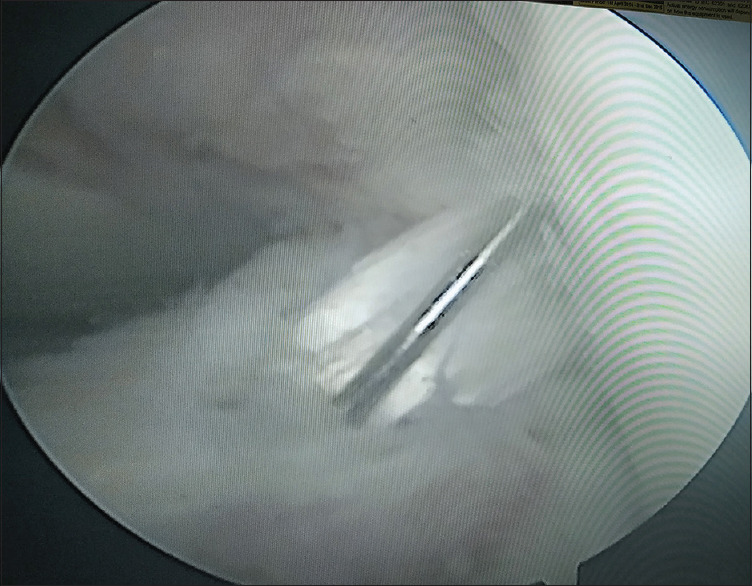

Introduction: Anterior cruciate ligament (ACL) is a common injury which has been conventionally managed by various graft reconstruction using bone patellar tendon bone, or quadruple hamstring autograft, to name a few. However, all these grafts are associated with many complications. Lately, peroneus longus tendon (PLT) autograft has shown promising results in this field, although there is still a dearth of data on its use. We, therefore, aimed at carrying out a study to evaluate the functional outcome and knee stability results of ACL reconstruction using PLT graft.

Patients and methods: Patients with a completely torn ACL were included in the study. The PLT was harvested, and graft length, thickness, and harvesting time were noted intraoperatively. Knee stability and functional scores were evaluated clinically and using Lachman test (primarily) and KT-2000 arthrometer and subjectively with International Knee Documentation Committee (IKDC) score at 6, 12, and 24 months (secondary outcome) postoperatively. Ankle scores were also recorded by making use of American Orthopedic Foot and Ankle Score (AOFAS)-Hindfoot Scale.

Results: Forty-eight patients met the inclusion criteria. The graft harvest time was 7.4 min (5-9 min). The mean thickness of the graft on doubling was 7.9 mm (7-9 mm). Ninety-six percent of the patients were satisfied with their results of the knee surgery, and 95% of the patients had no complaints of ankle joint. The mean IKDC score postoperatively was 78.16 ± 6.23, and the mean AOFAS score was 98.4 ± 4.1. None of the patients had any neurovascular deficit.

Conclusion: ACL reconstruction using PLT graft yields a good functional score (IKDC, KT-2000 arthrometer) even at 2-year follow-up. It is a safe and effective autograft option for ACL reconstruction.